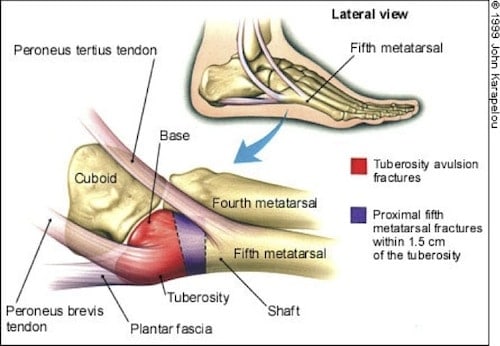

Children complaining of pain on the outside of the foot may have a condition known as Iselin’s disease or Iselin’s syndrome.

Generally children suffering from Iselin’s syndrome will report pain on the outer edge of the foot, at the prominence known as the styloid process. Some redness and swelling over the area will usually be present. Barefoot activity, jumping sports and narrow fitting footwear can be aggravating factors. Individual biomechanical factors need to be assessed and manageed, as splaying of the forefoot associated with flat feet, and walking on the outside of the feet with high arched/inverted feet are associated with Iselin’s disease.

It has been reported rarely, but is probably more common than appreciated. Clinically it can be confused with tendonitis, ankle sprains, fractures of the 5th metatarsal or even labeled as growing pains. It appears to be more common in athletically active, older children and adolescents, and more common in males. Early recognition and care management may prevent long-term complications such as non-union and subsequent pain.